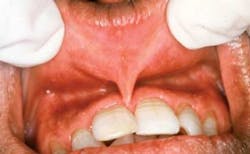

Figure 1: Submucous fibrosis noted with white striations.

You begin to search the possibilities for these observations and the etiology. As you question Deepak, you find that he has used areca nut and practiced betel nut chewing throughout his life. In this case, what you are observing is oral submucous fibrosis (SMF) resulting from chronic use of these products (Figure 1).

The use of such products stimulates the production of collagen by fibroblasts, and chronic use of the substances causes a cross-linking of the newly formed fibers. The body cannot break these down and they continue to strengthen. The white striations that are visible clinically denote what is happening microscopically. The tissue goes through several stages of progression to the premalignant state of submucous fibrosis.

Stage 1: Generalized stomatitis – This stage may present with ulcers, erythema, and vesicles. Because of the pigmentation of the areca nut, the teeth become stained, and the staining usually promotes questioning by the dental professional in trying to determine the etiology.

Stage 2: Fibrosis – The accumulations of fibrous bands are noted within the collagen. A white striation is also noted clinically. The deeper tissues are affected and eventually the muscles of the oral cavity tighten. The fibrosis makes the mouth restricted and continues to tighten as the tissue changes progress. Movement of the tongue is restricted and speech may be affected. Over time, the lips, soft palate, esophagus, and the oropharynx are affected as well.

Stage 3: The SMF is classified as premalignant leukoplakia-type lesions.